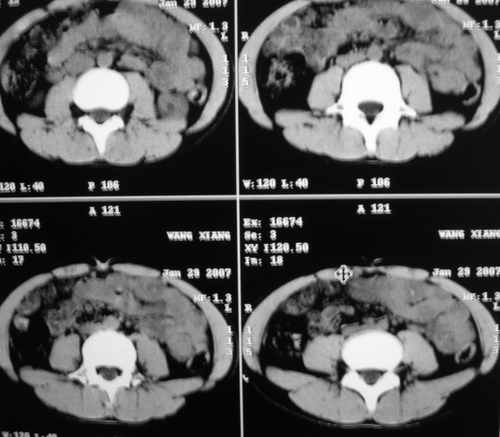

m 15y 外院b超发现左肾包块,遂来ct检查。

左肾外形明显小于右肾,左肾中上极后侧可见一等密度影,与肾分解不清,肾盂肾盏无扩张,先考虑:左肾发育不良,建议强化除外占位

左肾外形明显小于右肾,左肾中上极后侧可见一等低密度影,与肾分解不清,肾盂肾盏无扩张,先考虑:左肾发育不良,平滑肌脂肪瘤待排除。